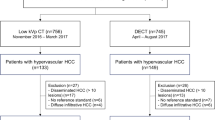

Forty patients with hepatocellular carcinomas were investigated with abdominal dual-energy CT. In each patient unenhanced and contrast-enhanced imaging with arterial und portovenous delay were performed. Hypervascular lesions were documented on arterial phase 80-kVp images, 140-kVp images, and the averaged arterial images by two radiologists. Subjective image quality (5-point scale, from 5 [excellent] to 1 [not interpretable]) was rated on all images.

Between April and August 2009, 40 consecutive patients (29 men, 11 women; mean age 64 years±10 years) underwent dual-energy CT (DECT) for evaluation of the liver for hypervascular lesions. This study was approved by our institutional review board and all patients provided written informed consent before participation.

The mean attenuation values of 80 kVp- and 140 kVp images for hypervascular hepatic lesions in the arterial phase were 119.3 ± 33.5 HU and 77.5 ± 16.6 HU, respectively. On averaged images attenuation was 91.7 ± 21.3 HU. This was significantly different from 80-kVp- and 140-kVp images (p <0.001 for both comparisons, Fig. 1). All other anatomical regions (liver, fat, aorta, muscle, air) differed significantly when the three datasets were compared (Table 1).

The number of detected lesions on 80-kVp, 140-kVp and averaged images was 3.4 ± 1.3, 1.4 ± 1.1, and 2.6 ± 1.2, respectively. These differences were significant (Table 2).

Liver delineation

In 25 examinations the liver underwent complete imaging with the 26-cm field-of-view detector; in 15 examinations liver coverage was incomplete. Potential incomplete coverage of liver parenchyma with the 26-cm field-of-view detector was rated as 0.58 ± 0.59 (range, 0–2; SD, 0.59) on the five-point scale.